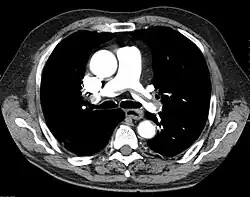

"Saddle" embolism on CT. The filling defect in the pulmonary artery is the clot.

A pulmonary embolism (PE) is an obstruction of the pulmonary arteries.[13] Deaths from PE have been estimated at ~100,000 per year in the United States. However, this may be higher in recent years.[16] Most often, the obstruction is a blood clot that traveled from elsewhere in the body. Most commonly, this is from a deep vein thrombosis (DVT) in the legs or pelvis.[13] Risk factors are conditions that increase the risk of clotting. This includes genetic (factor V Leiden) and acquired conditions (cancer).[17] Trauma, surgery, and prolonged bed-rest are common risks. COVID-19 is a recent risk factor.[18]

This obstruction increases the pulmonary vascular resistance. If large enough, the clot increases the load on the right side of the heart. The right ventricle must work harder to pump blood to the lungs. With back-up of blood, the right ventricle can begin to dilate. Right heart failure can ensue, leading to shock and death.[18]

A PE is considered "massive" when it causes hypotension or shock. A submassive PE causes right heart dysfunction without hypotension.[18]

A chest X-ray can rapidly identify a pneumothorax, seen as absence of lung markings. Ultrasound can show the lack of lung sliding. However, imaging should not delay treatment.[8] CT angiography is the standard of diagnosis of pulmonary embolism. Clots appear in the vasculature as filling defects.[18]